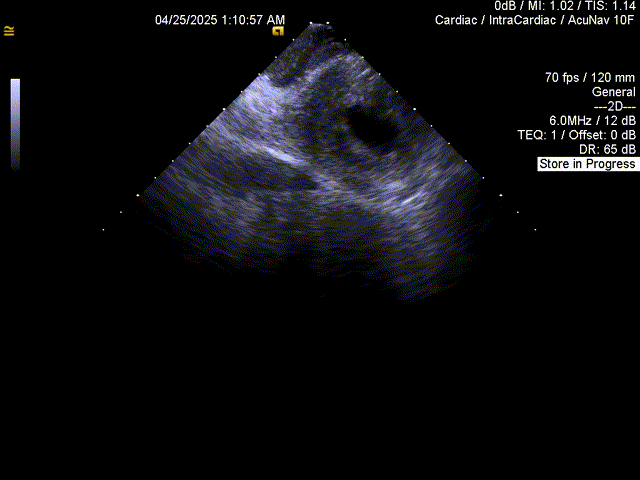

置入心腔内超声,成功房间隔穿刺

ICE引导房间隔穿刺

ICE下穿房间隔

ICE下评估PASS原则

封堵器位置及压缩比良好,多普勒检查无残余分流